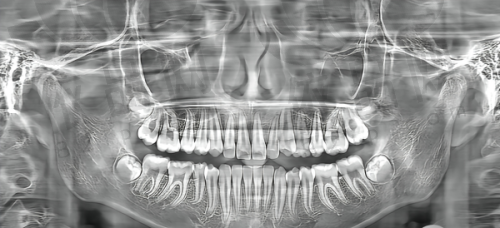

近期不少朋友向小编询问珠海摩尔口腔医院的情况,包括医院怎么样以及价格表收费情况。今天就针对这两个问题展开详细分析,看看珠海摩尔齿科有哪些优势、特色,性价比究竟如何!

作为一家资质正规的连锁牙科,摩尔口腔让人十分放心,大部分来此看牙的患者都给予了高度评价。各个门店能提供涵盖儿童齿科和成人牙齿治疗的诊疗服务,满足不同年龄段人群的看牙需求。

在硬件配备上,医院用心引进各种精良的仪器设备。医生团队实力强劲,在各个牙科领域经验多。所以,从各方面来看,摩尔齿科都是一家出色且值得面诊的齿科机构。